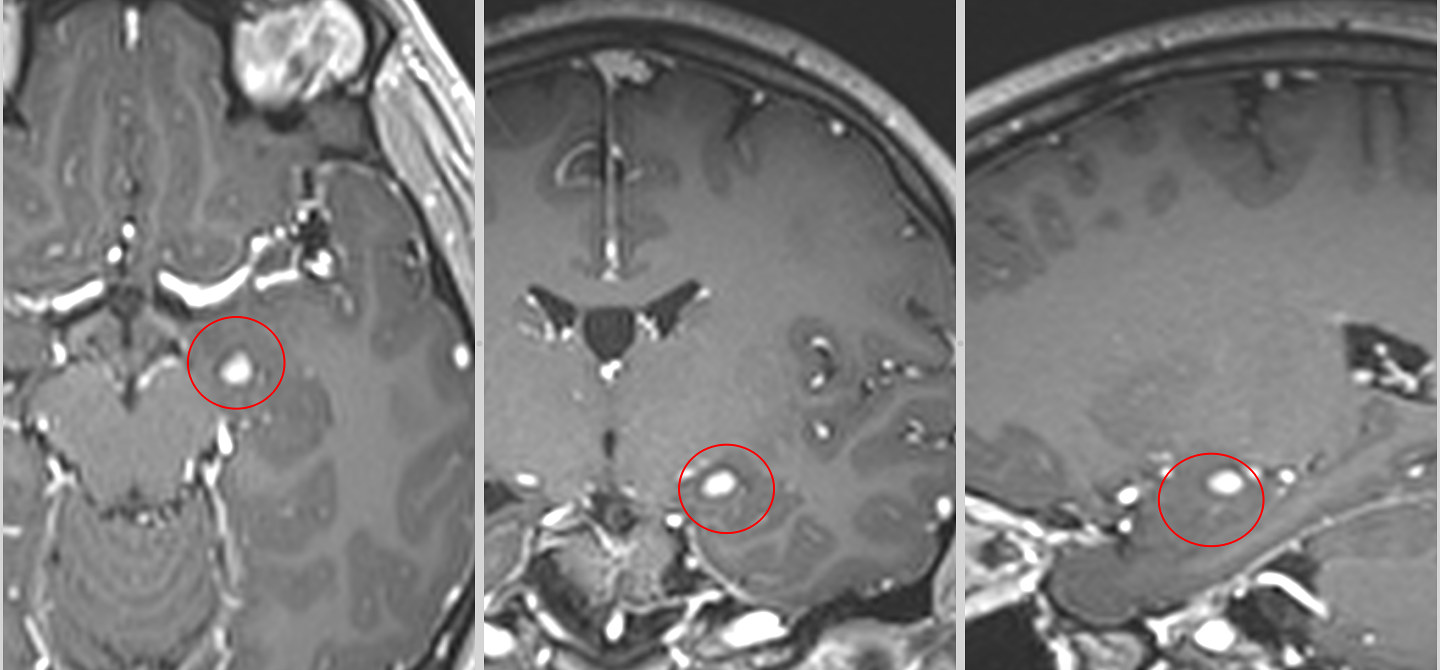

1. Gangliogliomul

- Epidemiologie: Cea mai frecventă tumoare glioneuronală. Afectează mai ales copiii și adolescenții.

- Localizare: Lobi temporali, frecvent implicând cortexul cerebral.

- Clinic: Epilepsie focală refractară, simptome neurologice progresive.

- Histologie: Prezența de neuroni maturi atipici și celule gliale. Poate prezenta mutația BRAF V600E.

- Tratament: Chirurgia este de obicei curativă. Rata de recurență este scăzută.

- Grad OMS: 1 (benign), dar poate progresa rar la formă anaplazică (grad 3).